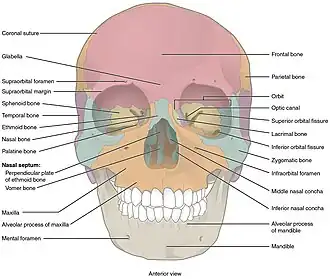

Anatomy

When discussing the anatomy of the face, it is often divided into thirds. The lower third extends from the chin to approximately the level of the upper teeth. The middle third continues from the teeth to just below the brow line. Finally, the upper third stretches from the brow to the hairline.[3]

The middle third of the face, or the midface, is the anatomical location in which Le Fort fractures occur. It comprises the maxillary bone, palatine bones, zygomas, zygomatic processes (of the temporal bone), ethmoid bone, vomer, nasal concha, nasal bones, and pterygoid processes (of the sphenoid bone).[2][3][4]

The maxillary bone contains important anatomical structures which are prone to injury during trauma. The maxillary sinuses are housed within the maxillary bone, and traumatic injury to these sinuses may cause sinus infections, and changes in eye placement and movement.[4] The infraorbital nerve (a terminal branch of CNV2) courses through the maxillary bone and provides sensation to the central face. Additionally, the maxillary bone contains the upper row of teeth (maxillary dentition). Occlusion, or the alignment of upper and lower teeth, is vital following midface trauma to ensure a patient is able to eat and speak.[2]